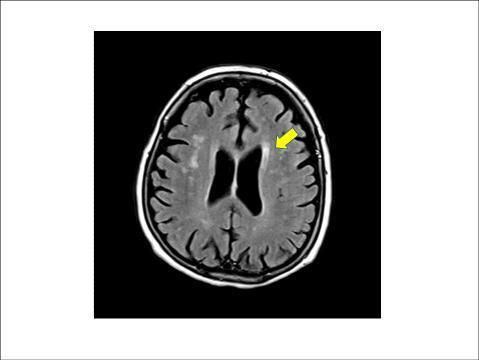

뇌 백질은 MRI 영상에서 뇌 중심부 옆으로 하얗게 보이는 부분을 말하는데, 이 백질에 퍼져 있는 작은 혈관들이 손상된 상태를 뇌 백질 변성이라고 한다. 또 무증상 뇌경색은 뇌 속 작은 혈관이 막혀 생기는 질환을 일컫는다.

이들 질환 모두 MRI에서 무증상의 병변으로 보이지만, 점차 뇌 노화가 비정상적으로 진행되면서 뇌졸중이나 치매 등 심각한 질환으로 이어질 수 있다.

뇌 백질 |